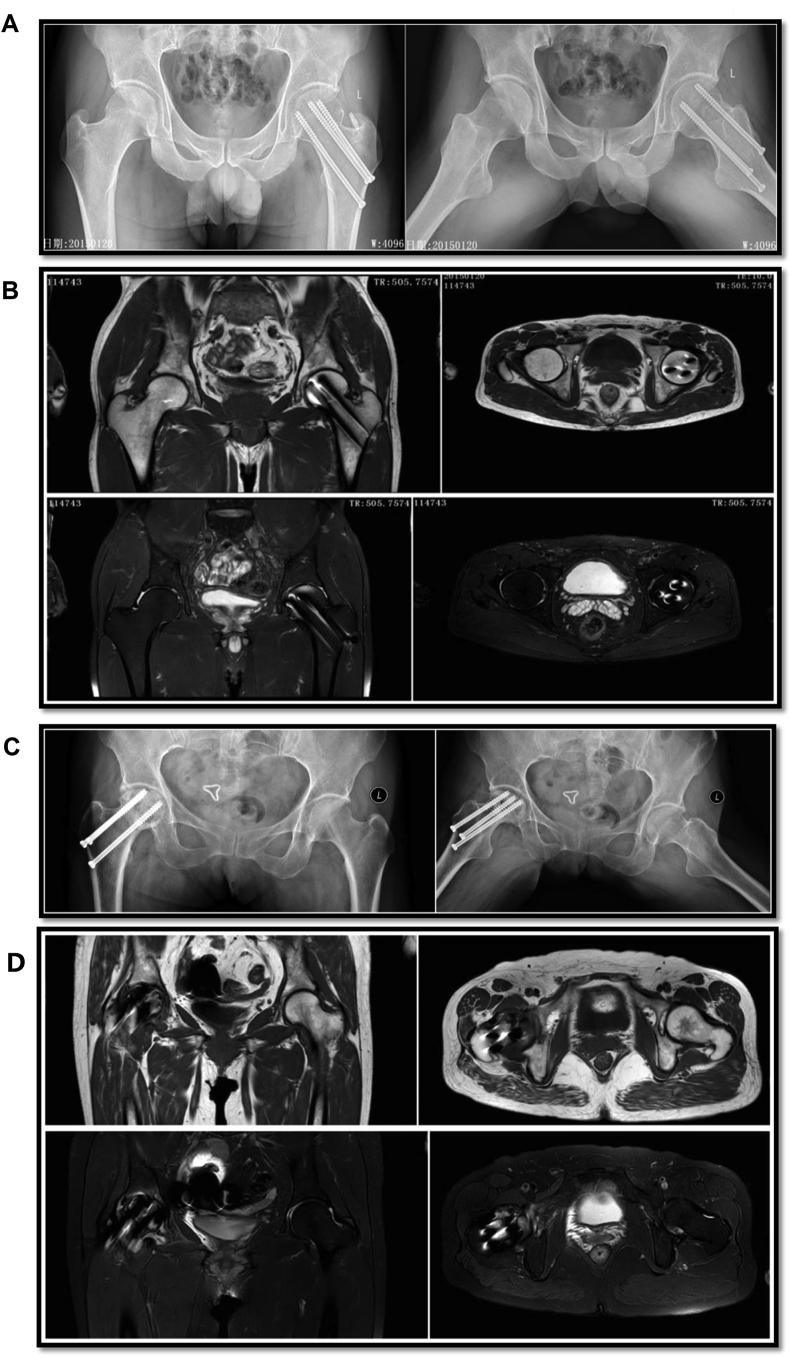

We aimed to identify specific circular RNAs (circRNAs) involved in bone repair of trauma-induced osteonecrosis of femoral head (TIONFH) and to explore the potential mechanism. CircRNA sequencing on the blood sample collected from patients with and without TIONFH was performed to select cirRNAs that were significantly differentially expressed, followed by qRT-PCR confirmation. Furthermore, the functions of one selected circRNA and the potential mechanisms in bone repair of TIONFH were validated based on the bone marrow mesenchymal stem cells (BMSCs) and osteoclast-like cells (OLCs) through CCK-8, flow cytometry, transwell assay, luciferase reporter assay, and western blot. A total of 234 upregulated and 148 downregulated differentially expressed circRNAs were identified, and qRT-PCR showed that circRNA_25487 was significantly upregulated in the peripheral blood of TIONFH patients. Luciferase reporter assay confirmed the binding effect between miR-134-3p and circRNA_25487. CircRNA_25487 suppression and miR-134-3p overexpression could promote cell proliferation and invasion while inhibited apoptosis of BMSCs and OLCs. miR-134-3p could target p21. CircRNA_25487 inhibited bone repair in TIONFH by sponging miR-134-3p to upregulate the expression of p21.

我们旨在鉴定参与创伤性股骨头坏死(TIONFH)骨修复的特定环状RNA(circRNA),并探索其潜在机制。对患有和未患有TIONFH的患者采集的血液样本进行circRNA测序,以筛选出差异表达显著的circRNA,随后进行qRT-PCR验证。此外,基于骨髓间充质干细胞(BMSC)和破骨细胞样细胞(OLC),通过CCK-8、流式细胞术、transwell实验、荧光素酶报告基因实验和蛋白质免疫印迹法,验证了一种选定的circRNA的功能及其在TIONFH骨修复中的潜在机制。共鉴定出234个上调和148个下调的差异表达circRNA,qRT-PCR显示circRNA_25487在TIONFH患者外周血中显著上调。荧光素酶报告基因实验证实了miR-134-3p与circRNA_25487之间的结合作用。抑制circRNA_25487和过表达miR-134-3p可促进BMSC和OLC的细胞增殖和侵袭,同时抑制其凋亡。miR-134-3p可靶向p21。circRNA_25487通过海绵吸附miR-134-3p上调p21的表达,从而抑制TIONFH的骨修复。